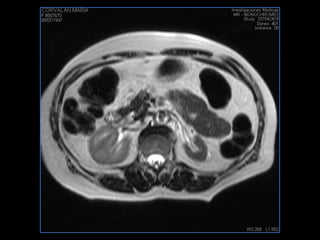

PROTOCOLO pancreas/ riñon AXIAL fat sat /AX in phase out phase AX T1 +SAG T2  COR T2, CON   GADOLINIO :  COR T1+AX T1(DIN) SAT: NO  FASE: RL THK: 4MM  COIL:  GAP: (FACTOR 1.4) 1MM FOV: 40 CM NEX:2 SINCRONIZACION RESPIRATORIA EN 3 O 4 CICLOS ALE

resonancia de abdomen